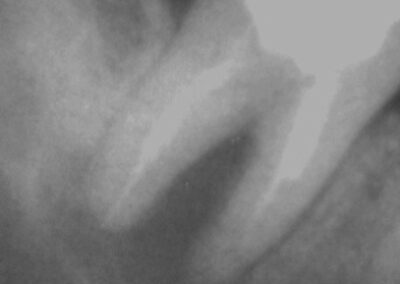

Interessant an dem folgenden Fall ist wiederum, dass die mesialen Kanäle bei der Revision nicht durchgängig waren. Nichtsdestotrotz ist der periapikale Prozess auch an dieser Wurzelspitze röntgenologisch und klinisch vollständig ausgeheilt. CHKM ist ganz offensichtlich ungemein kriechfähig.